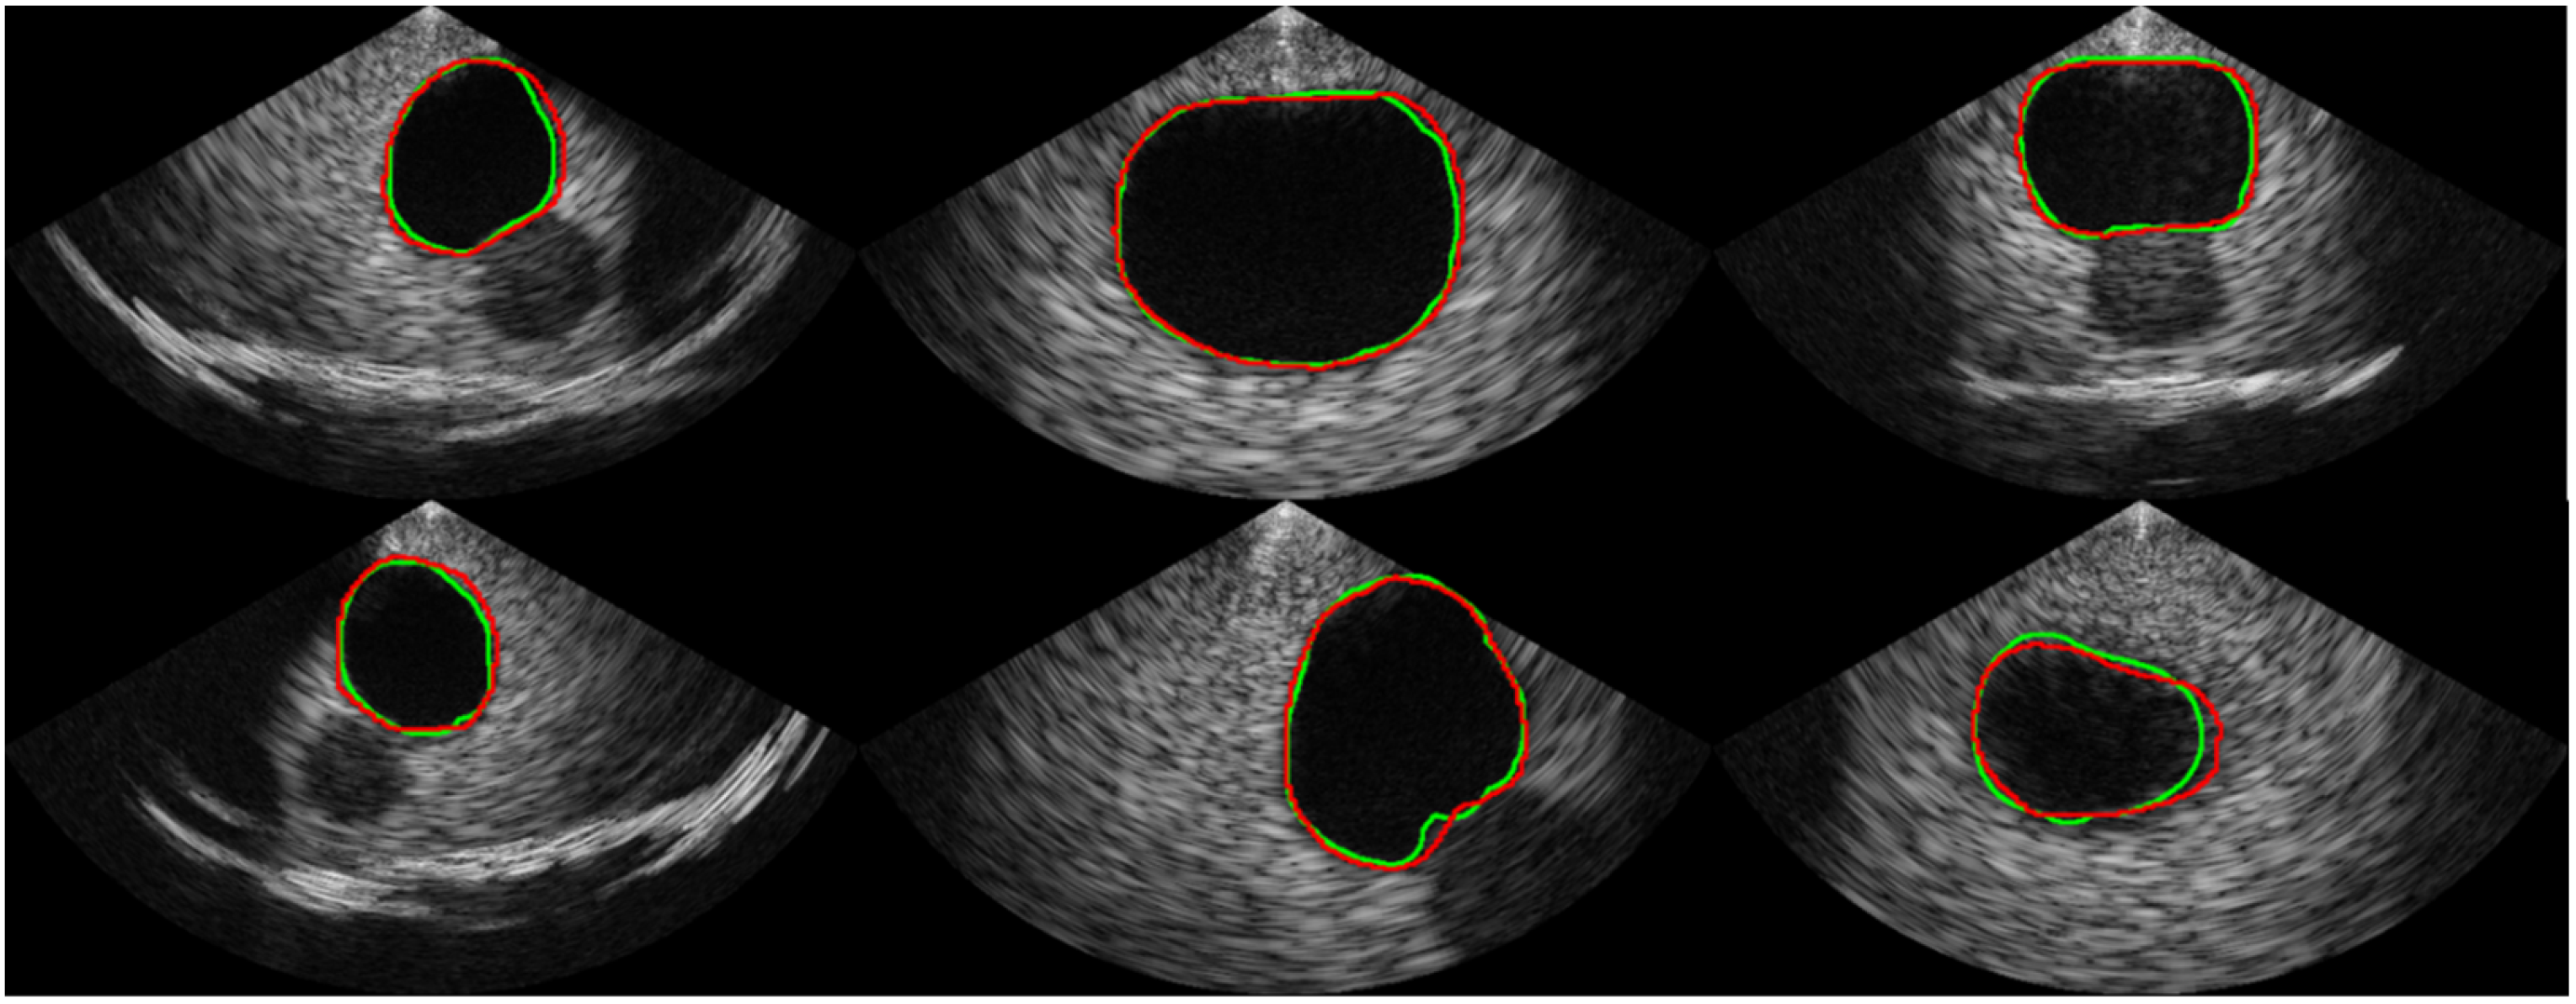

Table 1 shows the comparison of the proposed segmentation path with conventional CNN-based segmentation networks. U-Net, which is commonly used as a baseline for medical image segmentation, achieved an average Dice coefficient of 0.913 with a standard deviation of 0.124. The implemented U-Net had 8.56 million parameters and a throughput of 1.33 frames per second (FPS) in the SoC environment. In comparison, the Attention U-Net achieved a much higher Dice coefficient of 0.944 on average with a standard deviation of 0.075 but had a slower throughput than the U-Net, despite having fewer parameters. The recently introduced BiSe-Netv2 showed even higher Dice coefficients than both U-Net and Attention U-Net (i.e., an average of 0.958 and a standard deviation of 0.034) with even fewer parameters. However, BiSeNetv2 was slower than U-Net, running at less than 1 FPS. In contrast, the proposed method had significantly fewer parameters (i.e., 0.97 million) and could be executed at a much faster rate of approximately 8 FPS, which was 5.96x , 52.87x, and 13.44x faster than the U-Net, Attention U-Net, and BiSeNetv2, respectively. Although the proposed method had a slightly lower Dice coefficient than BiSeNetv2 (i.e., 0.954 ± 0.045 vs. 0.958 ± 0.034, respectively), the segmentation results from the proposed network are promising, as shown in Figure 6. The validation accuracy of the classification path was over 0.99, indicating high accuracy in the classification results, as shown in the confusion matrix in Figure 7.

Figure 6.

Examples of the segmentation result. The ground truth is represented by the green line, while the prediction from our proposed network is represented by the red line.